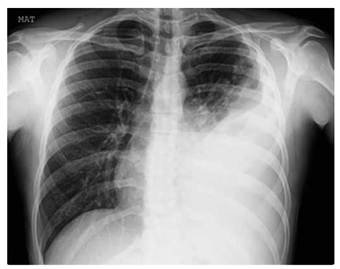

Paciente do sexo masculino, 58 anos, tabagista de 40 maços/ano, portador de DPOC moderado.

Procura pronto-socorro com febre há 3 dias, tosse produtiva com expectoração purulenta e dispneia progressiva. Nas últimas 6 horas, evoluiu com rebaixamento do sensório e intensa dificuldade respiratória. O exame físico na sala de emergência apresenta: PA: 92 × 60 mmHg; FC: 128 bpm; FR: 38 irpm; SatO₂: 82% em cateter nasal 5 L/min; T: 38,6 °C.

Escala de Glasgow: 12.

Estertores crepitantes difusos em hemitórax esquerdo e abolido em base.

Uso de musculatura acessória e tiragem intercostal.

Apresenta exames complementares: leucócitos: 18.400/mm³; creatinina: 1,9 mg/dL.

Gasometria em O₂: 5 L/min; pH: 7,28; PaO₂: 52 mmHg; PaCO₂: 58 mmHg; HCO₃⁻: 20 mEq/L; relação PaO₂/ FiO₂:110.

Radiografia de tórax a seguir:

Qual a conduta ventilatória mais adequada para esse paciente?